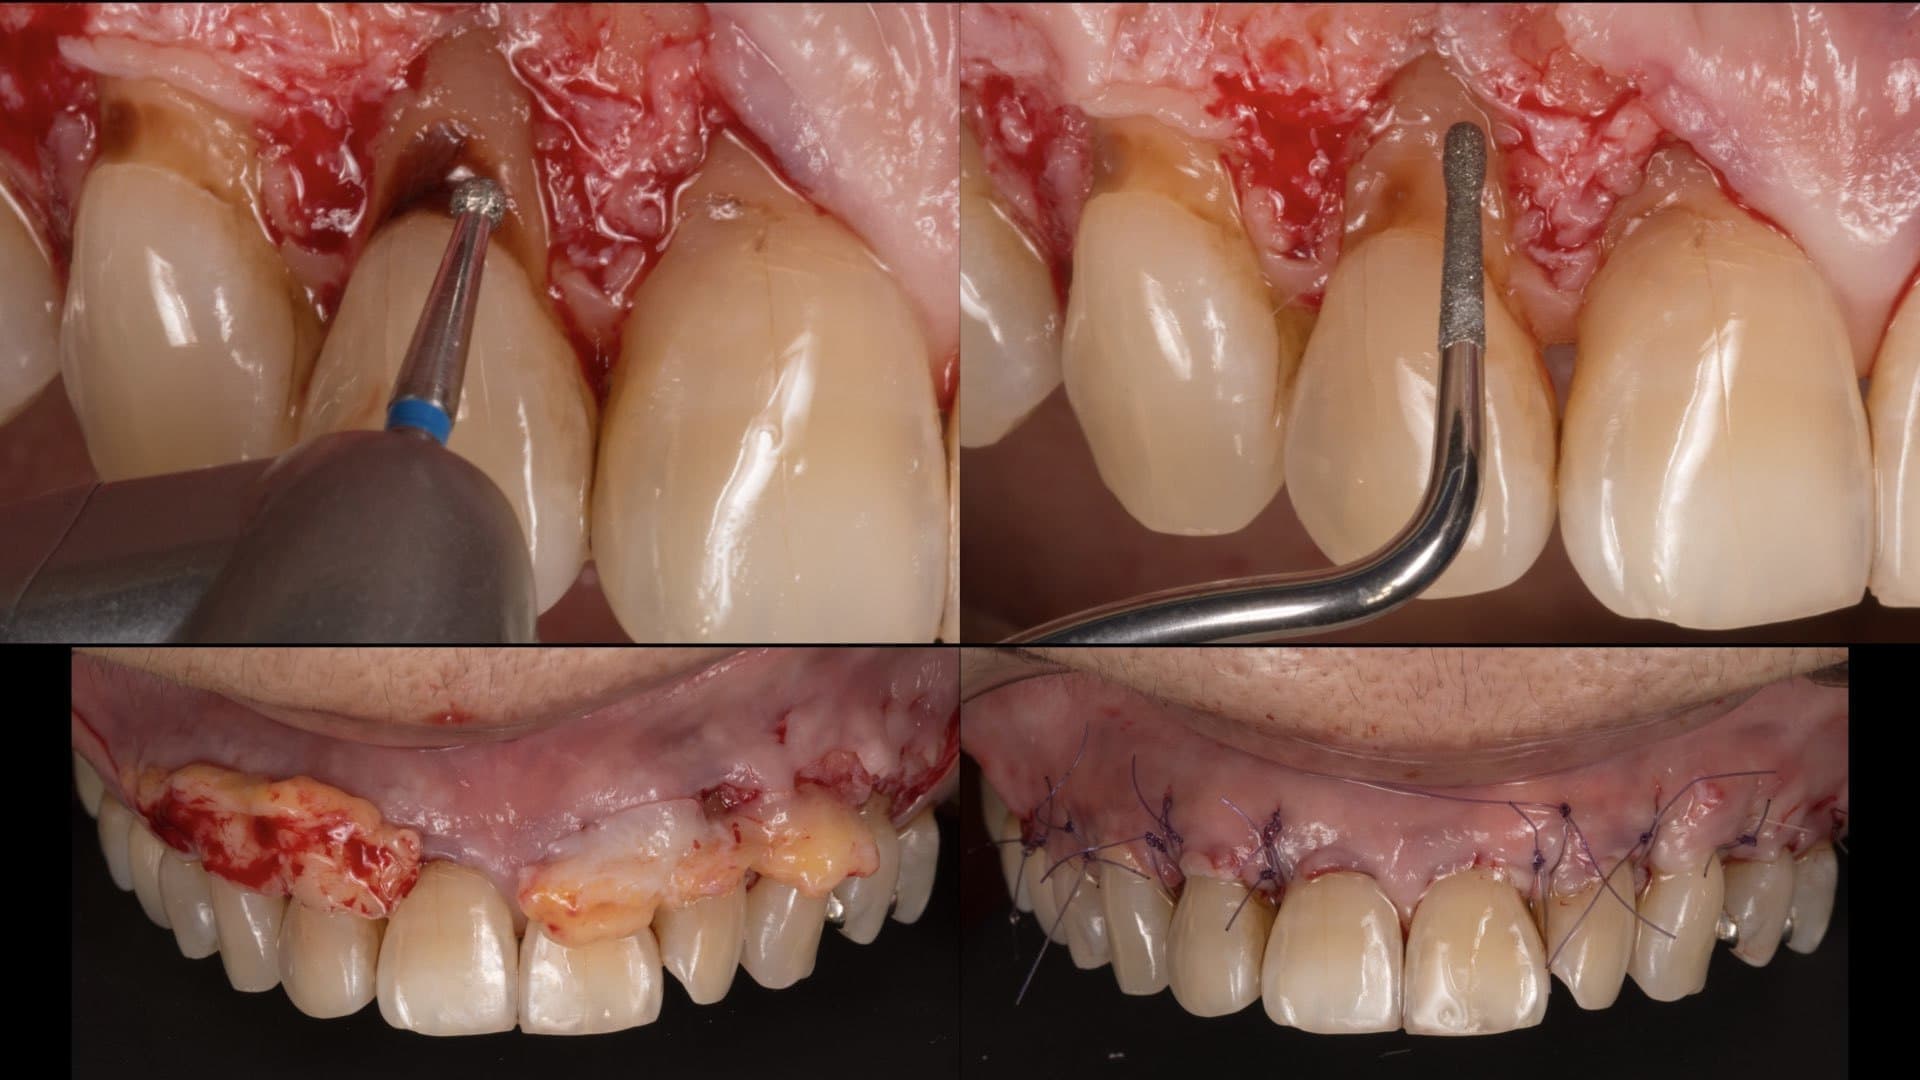

適切な治療を行えば、健康な口腔内を実現できます

専門医ではないと対応できない症例もあります